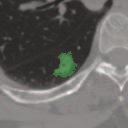

Deep learning based medical image segmentation models usually require large datasets with high-quality dense segmentations to train, which are very time-consuming and expensive to prepare. One way to tackle this challenge is by using the mixed-supervised learning framework, in which only a part of data is densely annotated with segmentation label and the rest is weakly labeled with bounding boxes. The model is trained jointly in a multi-task learning setting. In this paper, we propose Mixed-Supervised Dual-Network (MSDN), a novel architecture which consists of two separate networks for the detection and segmentation tasks respectively, and a series of connection modules between the layers of the two networks. These connection modules are used to transfer useful information from the auxiliary detection task to help the segmentation task. We propose to use a recent technique called "Squeeze and Excitation" in the connection module to boost the transfer. We conduct experiments on two medical image segmentation datasets. The proposed MSDN model outperforms multiple baselines.